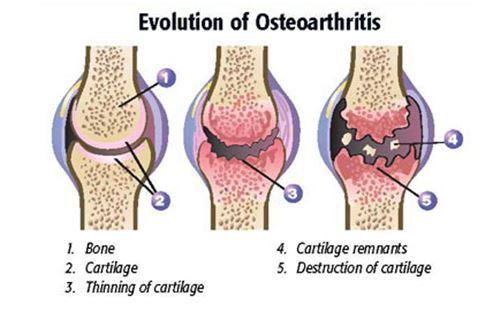

OA affects the joints of the horse, resulting in the slow progression of destruction to the cartilage lining the ends of the bones. It can affect one or multiple joints and can vary in severity.

This joint disease with multifactorial causes results in the progressive degradation and destruction of articular cartilage: the very thin layer of highly specialized connective tissue lining the ends of the long bones where they join. In young horses, OA is predominantly trauma-related.

For example, repeated cycles of athletic trauma, loss of stability or development of joint incongruities (e.g., secondary to fractures, ligament injuries, etc.), and remodeling and microfracture in the bone underlying the articular cartilage can all negatively impact normal articular cartilage. Similarly, normal forces on cartilage damaged via synovitis and capsulitis (i.e., inflammation of the lining of the joint and the capsule overlying the joint, respectively), the normal aging processes, or conditions such as osteochondrosis (failure of the bone that underlies articular cartilage to mineralize; can lead to osteochondritis dissecans, or OCD) can equally and negatively affect the cartilage in joints.

“Regardless of the underlying cause, the result is the physical breakdown of articular cartilage culminating in a hot, swollen, painful joint and loss of function,” he says.

The joint, where two bone ends meet are lined with cartilage, providing a smooth, almost frictionless, gliding surface. Inflammation (the “-itis” in arthritis) releases chemicals that breakdown the cartilage. As the cartilage is destroyed, the underlying bone becomes involved in the process. When bone becomes inflamed, it produces more bone (which is one reason why fractures can heal). But when bone is produced in a joint, movement becomes restricted, and painful.